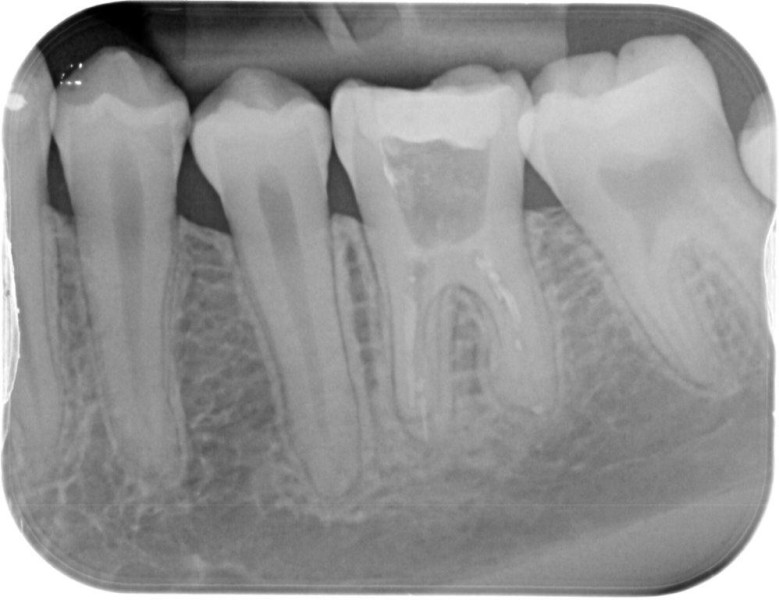

Molar retreatment